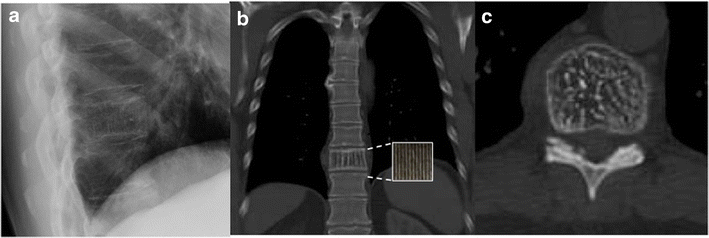

View Inverted Napoleon Hat Sign Background. Inverted magnified image of l5 showing the hat like contour of l5 vertebra. Radiograph of ls spine shows abnormal contour of the l5 vertebra.

Resources on inverted napoleon hat sign from pubget. Picture of napoleon wearing his hat in the inset. Find the perfect napoleon hat stock photos and editorial news pictures from getty images.

The license could not be verified: Spondylolisthesis napoleon hat sign inverted kick beater inverted cervical x ray. Chilaiditi sign (& syndrome) σύνδρομο κηλαϊδίτη * ( chilaiditi syndrome / colonic interposition 6 ): Inverted napoleon hat sign definition in the dictionary english.